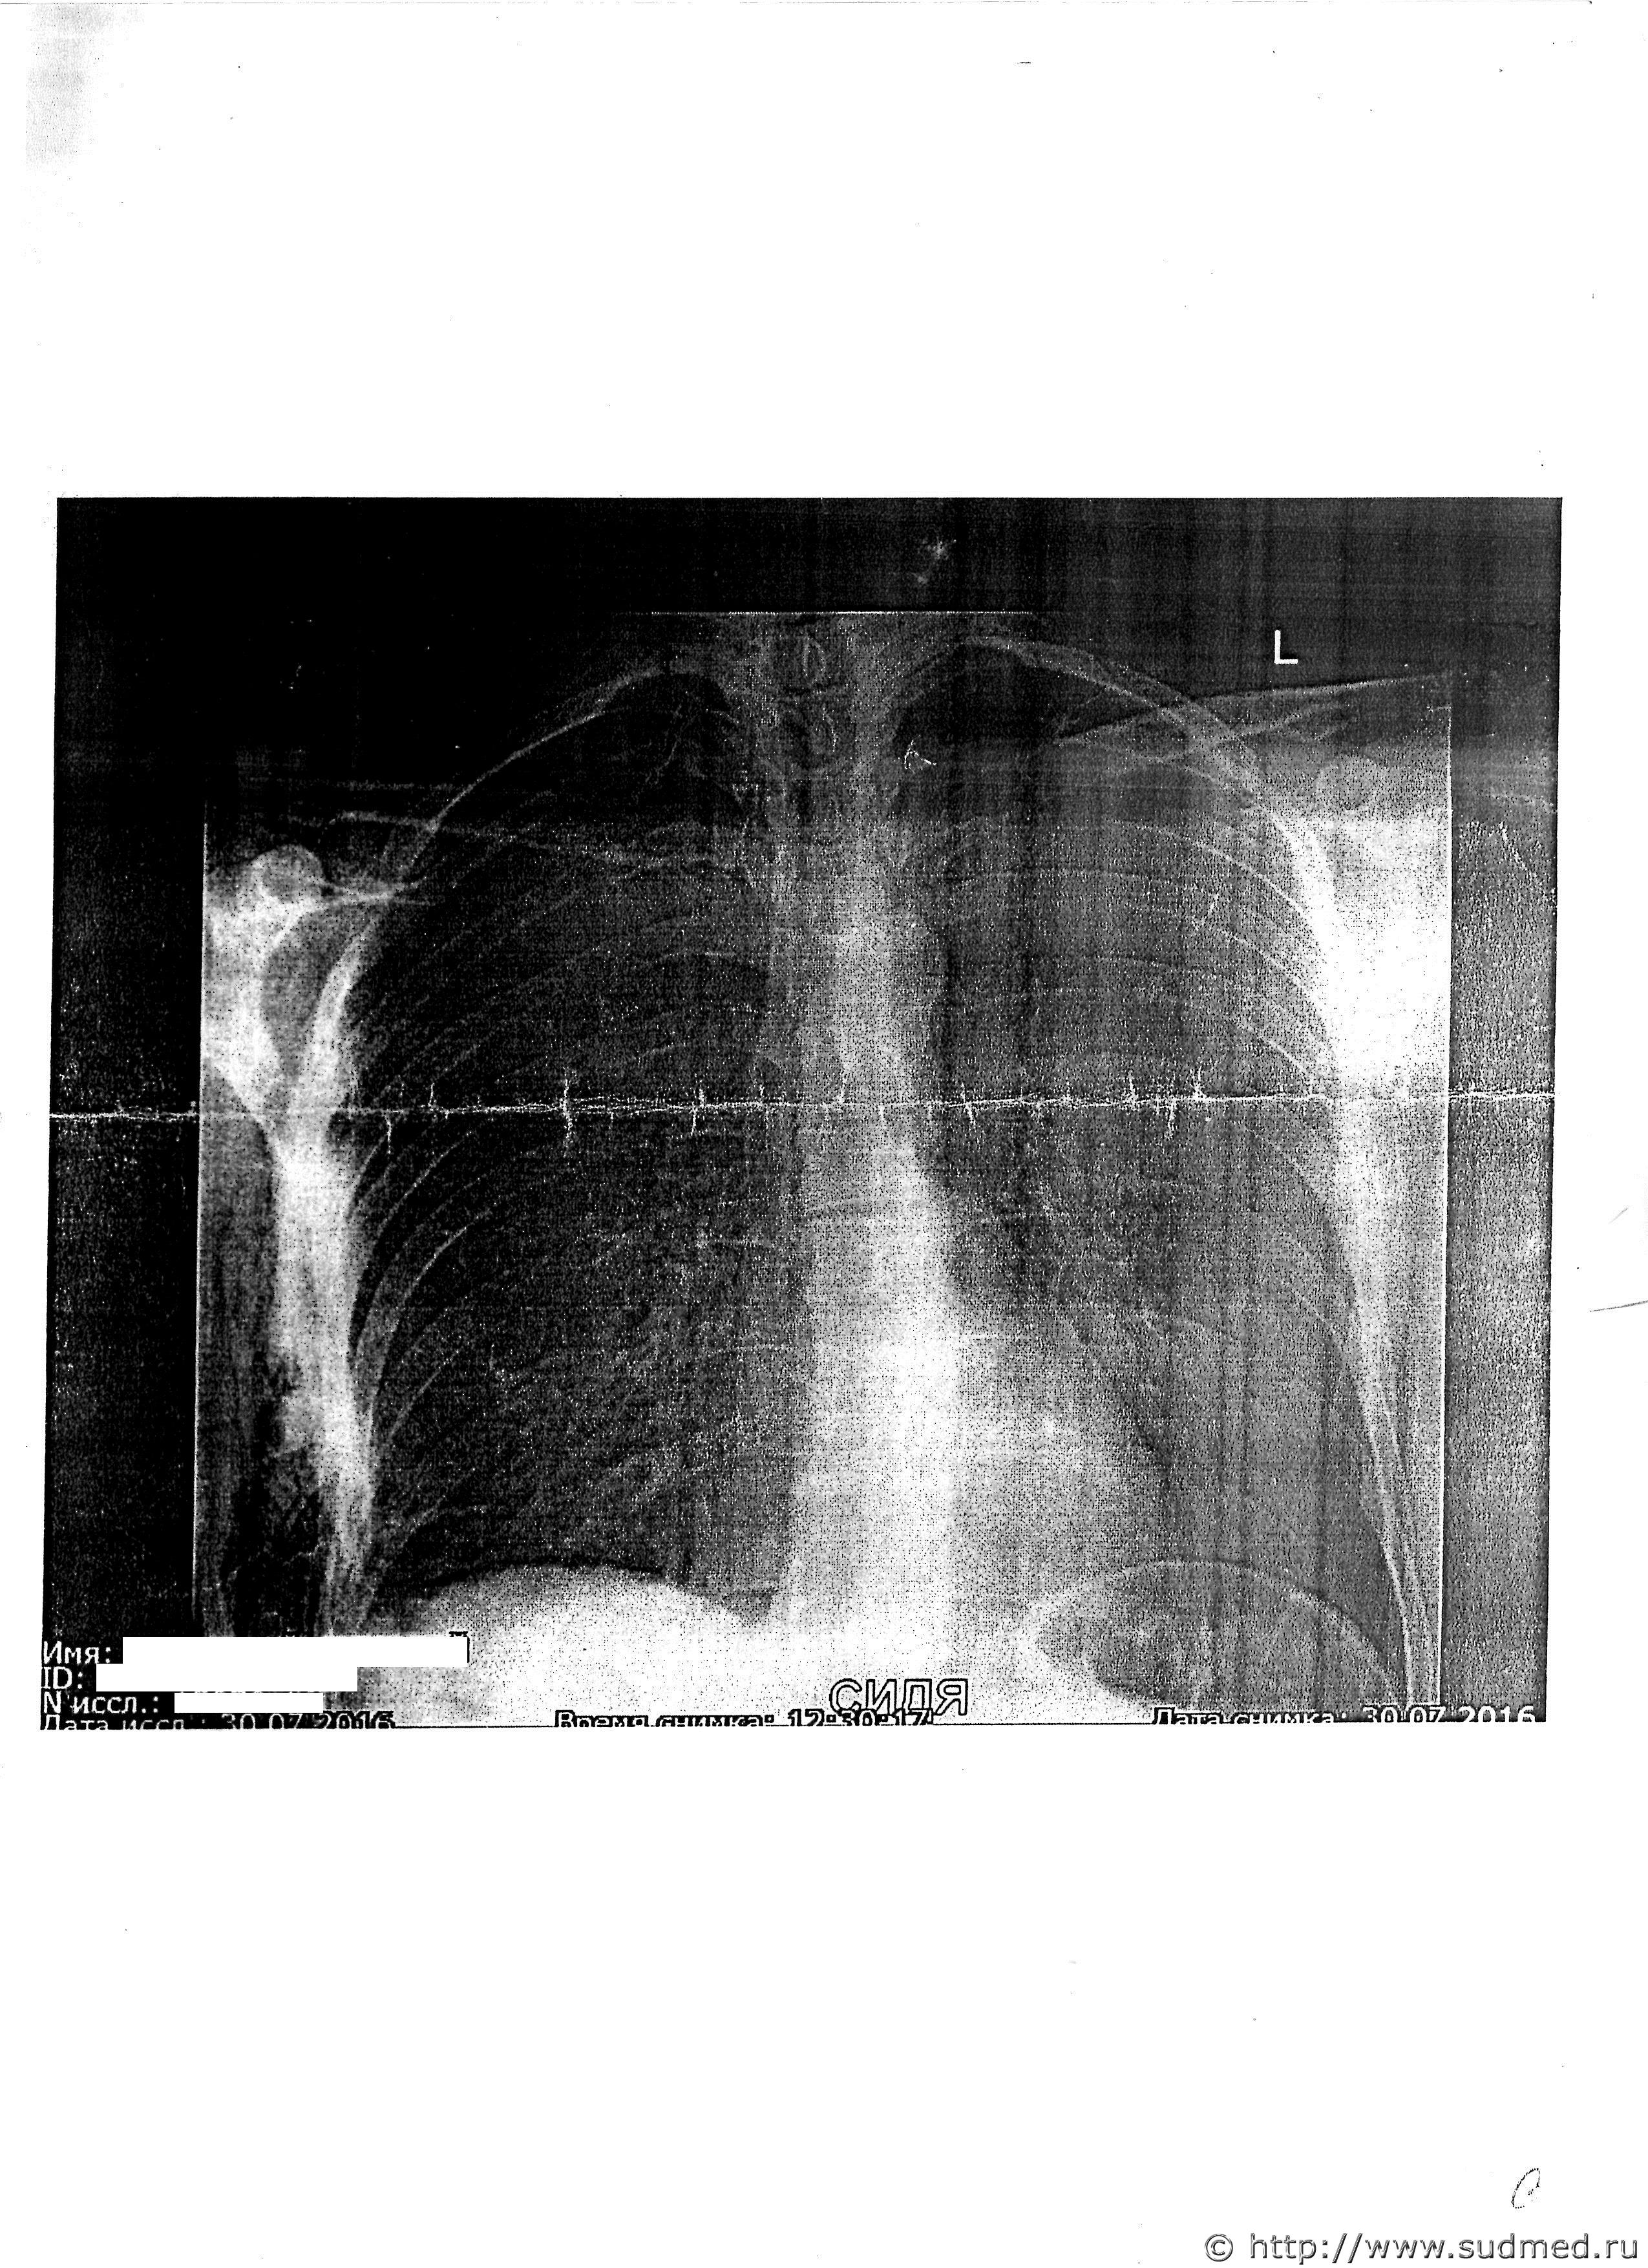

Доброго времени суток. Очень буду признателен мнению экспертов. Вот появились снимки и возникли вопросы по ним.

1. Подскажите, пожалуйста, можно определить повреждение и имеется ли разрыв лёгкого?

2. Может ли такое повреждение быть связано с повреждением париетальной плевры без повреждения самого лёгкого?

4.Можно ли по снимку определить - это пневмоторакс либо иное травматическое или посттравматическое явление?

5. Могло ли такое повреждение образоваться при падении с высоты собственного роста с приданием телу дополнительного ускорения (от удара)?

6. Могли ли переломы 5-8 ребер по средней подмышечной линии возникнуть от ударов кулаками лежащему на земле на левом боку человеку?

7. От чего могли образоваться такие переломы?

4. Фактически здесь есть: достоверные рентгенологические признаки пневмоторакса (воздух в плевральной полости из-за разрыва легкого), клинические признаки дыхательной недостаточности (одышка), обширная эмфизема мягких тканей груди, видимая на рентгенограммах и наблюдавшаяся клинически. Вполне достаточный комплекс клинико-рентгенологических признаков.

Рентгенологические признаки, характерные для ушиба легкого значительно отличаются от рентгенологических признаков пневмоторакса (воздуха в плевральной полости). Воздух может попасть в плевральную полость если только повреждена плевра. При "тупой травме груди" пневмоторакс возникает при разрыве легкого и легочной плевры. Изредка бывают заболевания, при которых возможен спонтанный ("самопроизвольный") пневмоторакс, например, при выраженном туберкулезном поражении легкого, при буллезной болезни. Признаки этих заболеваний будут видны на рентгенограммах. Когда проявлений этих заболеваний нет, а есть признаки тупой травмы груди, то пневмоторакс можно считать травматическим.